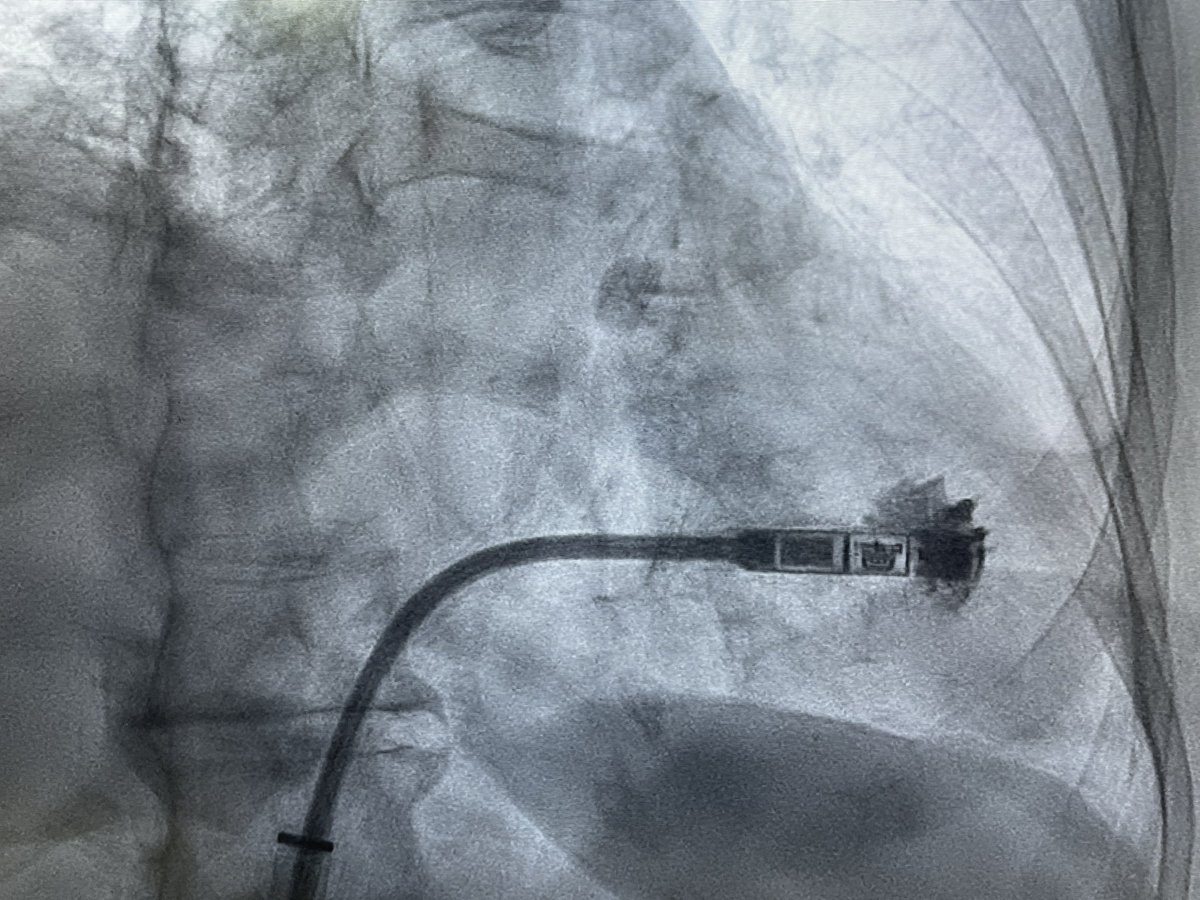

Dual chamber Leadless AVEIR pacemaker at Apollo Chennai - first in Tamilnadu and Apollo Group. - innovative, revolutionary, minimally invasive solution that ensures faster recovery and lasting comfort with physiological pacing. @Pacemaker @Apollo_Chennai @AbbottNews